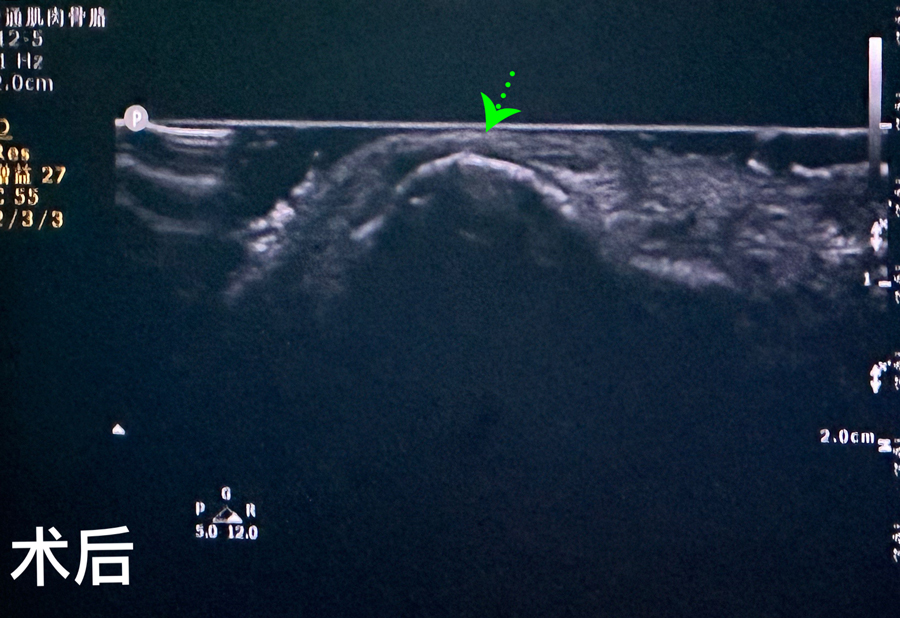

8月15日,彬彬家长在辗转多家医院后,听说啪啪网 有鼻骨骨折复位新技术,立即带彬彬赶到医院。此时,距离彬彬鼻骨骨折已经过去一周了。就诊时,彬彬鼻部肿胀已经消退了,能看到他的鼻梁是向左侧偏曲的,妈妈特别希望孩子的鼻梁能恢复到从前高挺、居中的状态。国家儿童医学中心、北京儿童医院耳鼻喉头颈外科常驻专家、啪啪网 副院长张薇,啪啪网 耳鼻喉科主任李莉萍为其进行鼻部检查,并结合鼻骨CT全面评估后,决定采用超声引导下鼻骨骨折复位术,以实现精准复位,使彬彬的面容不受影响。8月16日,张薇副院长、李莉萍主任及手术室、麻醉科医护人员组成手术团队,为彬彬进行手术。术中,医生在超声引导下应用复位器对游离骨片进行复位调节,使错位的鼻骨重新连续。10分钟后,手术顺利完成,复位后的鼻子外观无畸形。术后,彬彬接受抗感染治疗48小时,情况稳定,顺利出院。

相比较传统凭经验及手感的鼻骨复位术,超声引导下的手术复位能更精准定位到损伤部位,如医生的“透视眼”,实现手术可视化,使医生在术中可准确看到鼻骨断端的对合情况,在“精准、微创、美观”上得到极大优化和提升。患儿无伤口、恢复快。术前和术后鼻骨错位及对合情况B超均有图片准确显示,让家长也能看明白,患儿和家长的心理负担明显减轻不少,改善了就医体验。